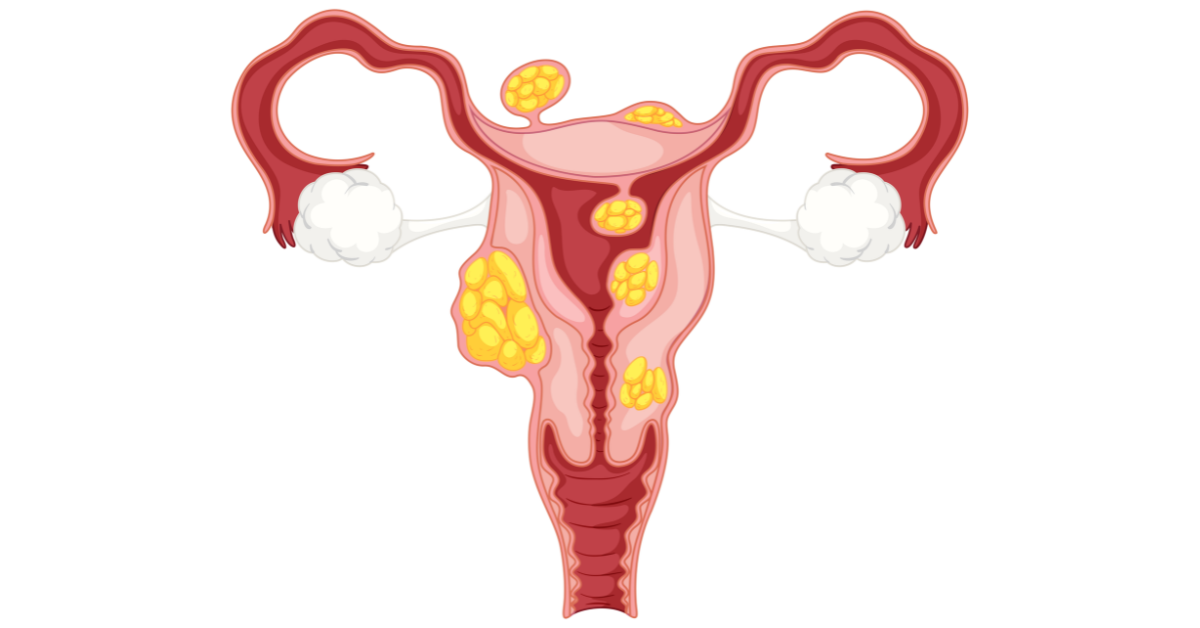

Uterine fibroids are non-cancerous growths that develop in or around the uterus. They are common among women during their reproductive years. Fibroids can vary in size and number, and many women may have them without noticing any symptoms. However, in some cases they can cause discomfort, heavy menstrual bleeding, or fertility problems.

These tests help determine the size, number, and location of fibroids and assist doctors in choosing the most suitable treatment plan.

Treatment for uterine fibroids depends on the severity of symptoms, the size of the fibroids, and a woman’s overall health. In some cases, fibroids that cause no symptoms may only require regular monitoring.